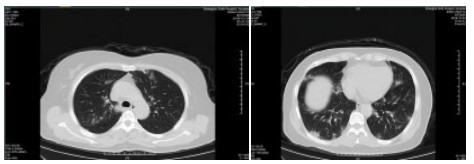

| 图 4 患者,男性,59岁,湖北籍,春节回乡探亲返沪,发热2 d入院,体温37.8℃, 乏力,既往体健。血白细胞总数及淋巴计数正常,甲型、乙型流感筛查阴性,新型冠状病毒核酸检测阳性。肺部CT提示双肺多发磨玻璃结节,病灶贴近胸膜伴支气管充气征及血管充血、增粗,可见部分纤维条索影 Fig 4 Case 4, male, 59 years old, born in Hubei Province, returned to Shanghai during the Spring Festival. He was hospitalized 2 days after fever, with a body temperature of 37.8℃ with fatigue. Normal WBC and lymphoid count, negative influenza A and B virus screening, positive novel coronavirus nucleic acid test. Lung CT showed multiple ground glass nodules in both lungs. The focus was close to the pleura, accompanied by bronchiectasis, hyperemia and thickening of blood vessels. Some fibrous bands could be seen |

| 图 5 患者,女性,44岁,沪籍,发病前10 d内有与确诊NCP患者接触史。出现发热,体温38.5℃,乏力,伴肌肉酸痛,既往体健。血白细胞总数及淋巴计数正常,甲型、乙型流感筛查阴性,新型冠状病毒核酸检测阳性。肺部CT提示双肺多发磨玻璃结节,病灶贴近胸膜伴支气管充气征及病变内血管充血、增粗 Fig 5 Case 5, female, 44 years old, born in Shanghai, had contact history with NCP patients within 10 days before the onset of the disease. Her body temperature was 38.5℃, with fatigue, muscle ache, previous physical fitness. Normal WBC and lymphoid count, negative influenza A and B virus screening, and positive novel coronavirus nucleic acid test. Lung CT showed multiple ground glass nodules in both lungs. The lesions were close to the pleura with bronchiectasis and congestion and thickening of blood vessels in the lesions |